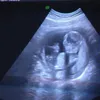

Hari ini, Jumat (5/12) Oki Setiana Dewi melahirkan putri pertamanya. Bayi mungil itu lahir dengan berat 3,410 kg dan panjang 51 cm dan tentu saja membawa kebahagiaan bagi Oki dan suaminya, Ory Vitrio. Seperti apa wajah bayi perempuan Oki? Yuk, simak di sini...

Oki Setiana Dewi melahirkan putri pertamanya, Jumat (5/12).